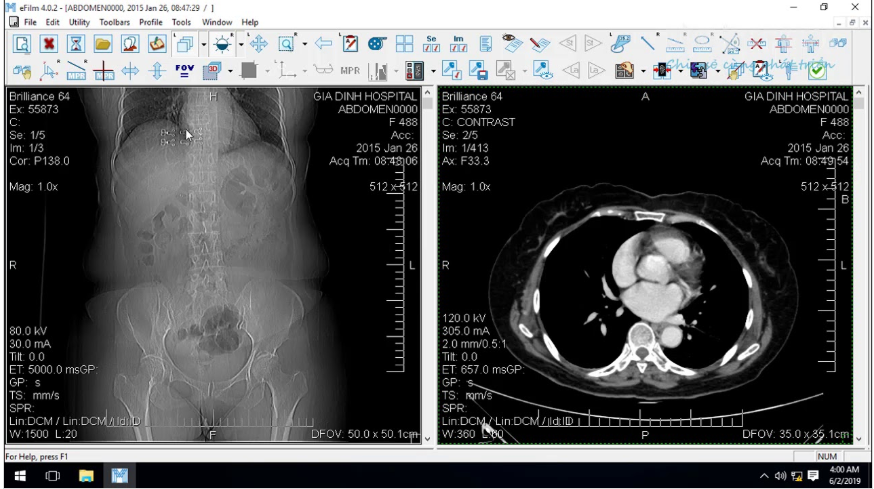

O eFilm Workstation é um software avançado para visualização de imagens médicas no formato DICOM. Desenvolvido pela Merge Healthcare (atualmente parte da IBM Watson Health), é amplamente utilizado por radiologistas, ortopedistas, cardiologistas e outros profissionais que dependem de imagens médicas detalhadas para diagnóstico.

O eFilm faz parte do conceito de PACS (Picture Archiving and Communication System), permitindo que imagens médicas sejam armazenadas, recuperadas e analisadas digitalmente, substituindo os antigos métodos baseados em filmes radiológicos.

Comparação de exames anteriores e atuais na mesma tela

A Reconstrução Multiplanar permite visualizar imagens volumétricas nos planos axial, sagital e coronal simultaneamente, facilitando a análise anatômica tridimensional.